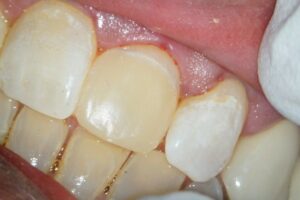

Der provisorische Aufbau erfolgte durch den Endodontologen mit vorab gefertigtem Silikonschlüssel mittels Tetric Flow und Ceram A3,5 als Abschluss der Single-Visit-Behandlung. Die endgültige Krone konnte am 12. Juni 2025 eingegliedert werden.